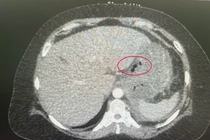

ho-1-nam1.jpg

Hình ảnh hạt sapoche trong đường tiêu hoá khiến bệnh nhân ho dai dẳng - Ảnh BVCC